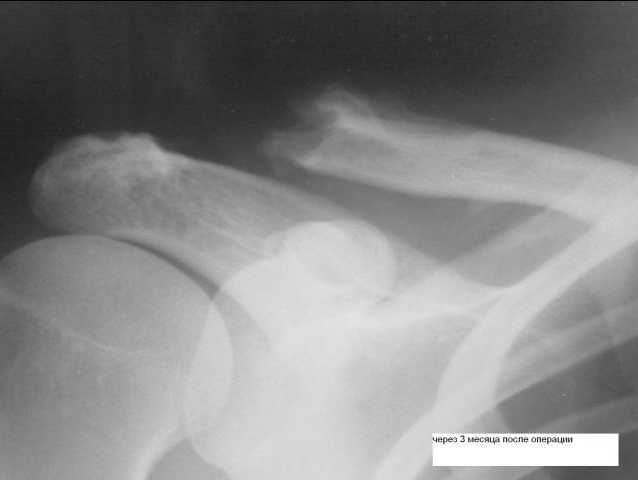

Недавно наткнулся на такого рода "новшество" - пластинка от АО для фиксации разрывов акромеально-ключичных сочленений.

фото приложил.